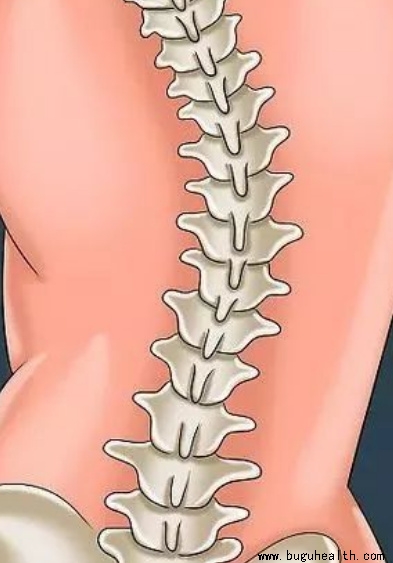

- 脊椎侧弯是一种常见的骨骼问题,在站姿下,不管从正面或背面看,正常的脊椎排列应该是身体左右两边对称,并且正常的脊椎排列从上到下是呈一直线的。.....

- 布骨医学科普:脊柱侧弯的康复功能锻炼方法! BuGuRMC布骨康复医疗中心 ,2023-06-26

- 脊柱侧弯是非常常见的一个问题,那么,如何简单的判断一个人是否有脊柱侧弯呢?如果你患有背部疼痛或轻度脊柱侧弯,或者你想预防脊柱侧弯,请开始下面的练习。.....